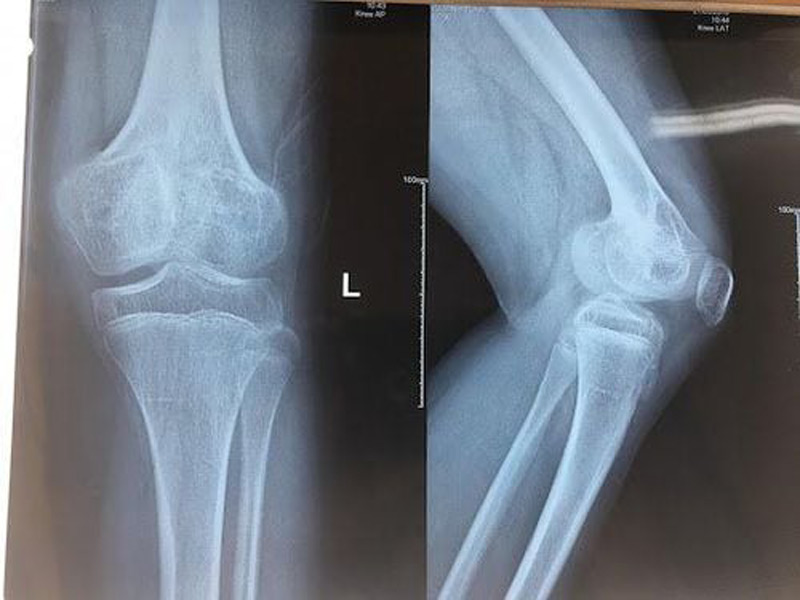

Chẩn đoán

- Chụp X-quang: Thường được sử dụng để xác định gãy xương. Tuy nhiên, trong một số trường hợp, đặc biệt là gãy loại I và V, X-quang có thể không phát hiện rõ ràng.

- So sánh với bên đối diện: Chụp X-quang cả hai bên để so sánh có thể giúp phát hiện gãy xương.